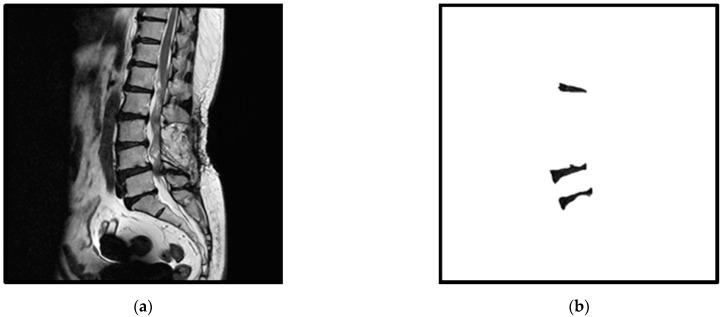

通过两阶段多分辨率U-Net模型实现特定椎间盘的自动分割

Automatic Segmentation of Specific Intervertebral Discs through a Two-Stage MultiResUNet Model.

The automatic segmentation of intervertebral discs from medical images is an important task for an intelligent clinical system. In this study, a deep learning model based on the MultiResUNet model for the automatic segmentation of specific intervertebral discs is presented. MultiResUNet can easily segment all intervertebral discs in MRI images; however, when only certain specific intervertebral discs need to be segmented, problems with segmentation errors, misalignment, and noise occur. In order to solve these problems, a two-stage MultiResUNet model is proposed. Connected-component labeling, automatic cropping, and distance transform are used in the proposed method. The experimental results show that the segmentation errors and misalignments of specific intervertebral discs are greatly reduced, and the segmentation accuracy is increased to about 94%. The performance of the proposed method proves its usefulness for the automatic segmentation of specific intervertebral discs over other deep learning models, such as the U-Net, CNN-based, Attention U-Net, and MultiResUNet models.

摘要